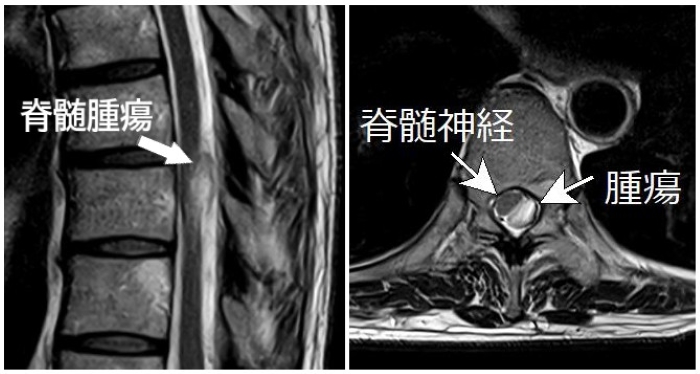

画像の患者さんは50代女性の方ですが,半年前から左側胸部の痛みを自覚,症状が続いているけど内科的には異常なしと言われているとして当院受診されました.胸椎MRI検査施行したところ第9胸椎の高さに脊髄腫瘍がみられ(下図),これが神経を刺激して肋間神経痛の原因になっていると診断しました(御本人からMRI画像掲載の許可を得ています).

別の70代女性の方は数年間続く右側胸部痛があり内科,婦人科,皮膚科など数カ所の病院で調べても異常ないと言われ原因がわからず困っていると来院されましたが,同じように脊髄腫瘍が原因の肋間神経痛でした.どちらの方も外科治療できる医療機関に紹介させて頂きました.